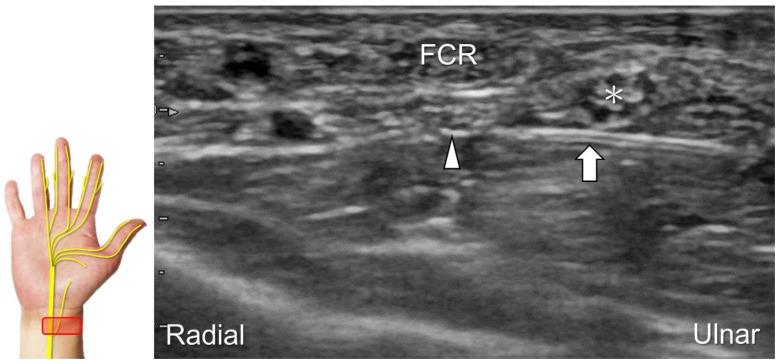

超声已成为一种极具价值的工具,用于腕部区域周围神经病变的成像,特别是对于诸如腕管综合征和尺神经管综合征等常见病症。大量研究表明,神经在卡压部位近端肿胀、边界不清和平扁是神经卡压的特征。然而,关于腕部和手部的小神经或终末神经的信息却很匮乏。本文旨在通过全面概述这些神经卡压的扫描技术、病理学和引导注射方法来填补这一知识空白。本综述详细阐述了正中神经(主干、掌皮支和返支)、尺神经(主干、浅支、深支、掌尺皮支和背尺皮支)、桡浅神经、骨间后神经、掌总/指固有神经和背总/指固有神经。一系列超声图像用于详细说明这些技术。最后,超声检查结果补充了电诊断研究,有助于更好地理解整个临床情况,而超声引导下的干预措施对于治疗相关神经病变是安全有效的。